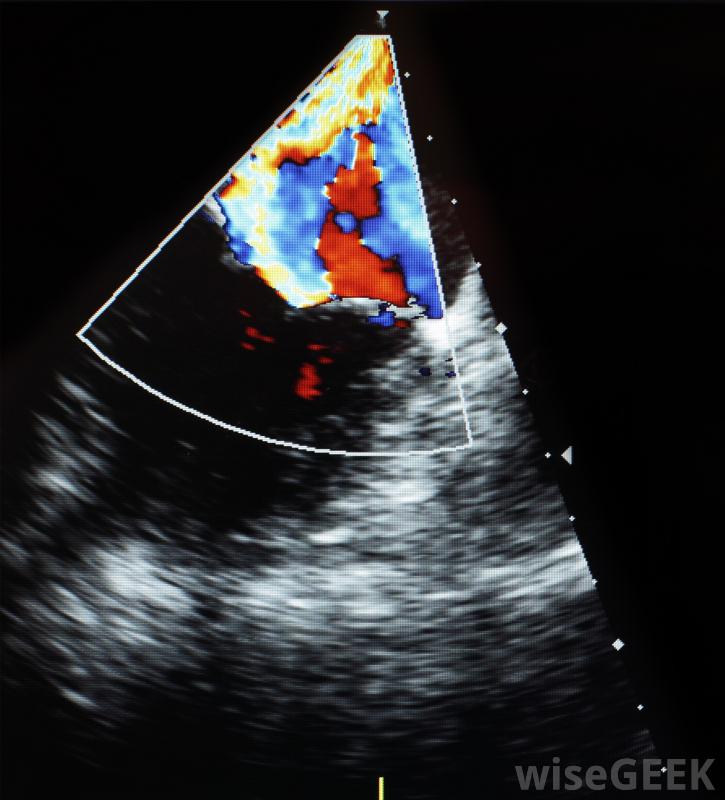

警察雷达枪使用多普勒技术多普勒测试在怀孕期间也用于监测血流。从母亲到婴儿的适当流量对婴儿的健康至关重要。该测试还允许医生监测和评估婴儿的心跳。这台机器实际上可以租给准父母,让他们在家里进行多普勒测试和倾听有时进行彩色多普勒超声检查,将声波结果转换成彩色结果,彩色检查有时用于识别已识别的癌性肿瘤因为它们通常显示血流量增加。虽然医生对这两种检查都很在行,彩色版本通常更容易阅读。多普勒测试几乎不需要患者准备。患者只需从待测区域脱掉任何衣物。由于尼古丁会影响多普勒测试结果-因为它会导致静脉收缩,所以病人可能需要在测试前一段时间内禁烟。作为一种非侵入性测试,多普勒测试几乎不会引起任何不适,也几乎没有风险

多普勒超声机利用多普勒效应产生运动图像。